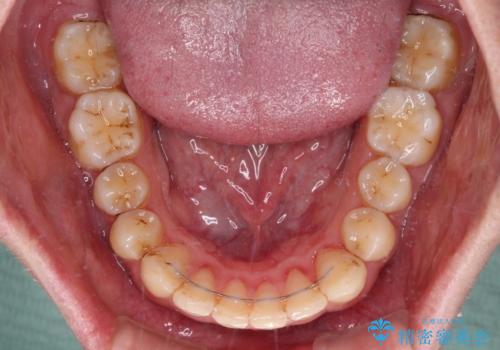

前歯のデコボコをスッキリ改善 インビザライン矯正

- 上下前歯のデコボコを気にして来院された患者様です。

全体的に叢生は軽度であったため、インビザラインにて矯正治療を行うこととしました。

デコボコの改善はもちろん、下顎前歯が隠れてしまうディープバイトも一緒に改善することができ、奥歯への負担を軽減することができました。